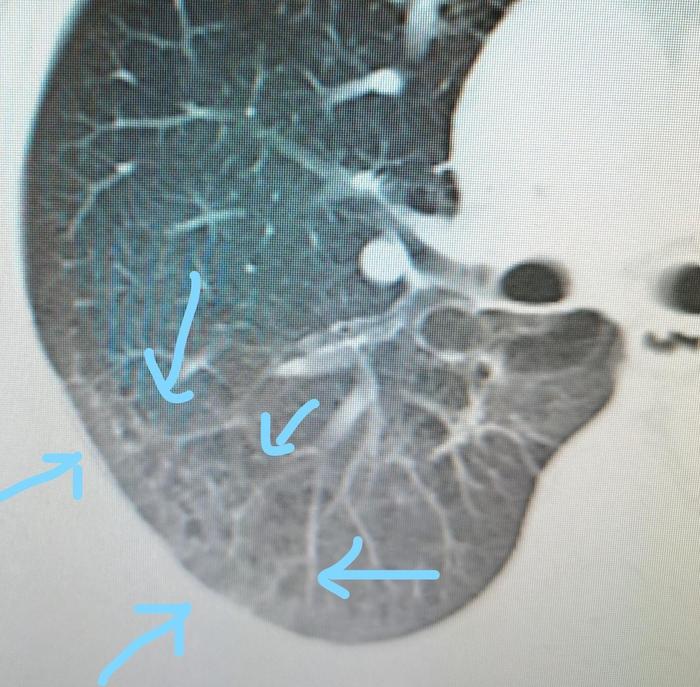

七、胸膜下长条状磨玻璃影,间质性肺炎

胸膜下长条状磨玻璃影,里面有小空洞。属于间质性肺炎的一种表现。